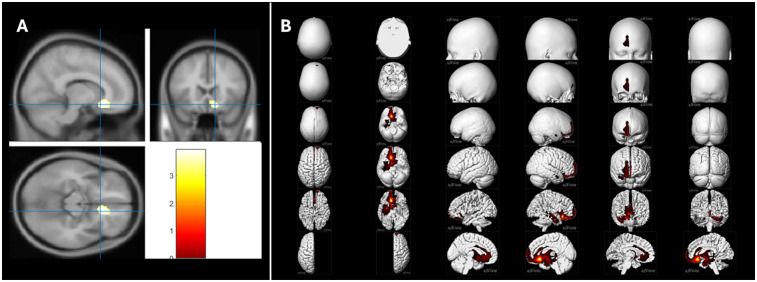

Results: A significant negative correlation was found between daily negative-emotion scores and metabolism in the right ventromedial prefrontal cortex (vmPFC) and anterior cingulate cortex (ACC), key regions of the brain's fear circuit. Inter-regional correlation analysis (IRCA) of metabolic connectivity from the right vmPFC/ACC further revealed a right limbic-dominant network including the amygdala, hippocampus, thalamus, and basal ganglia.

Discussion: These findings highlight the sensitivity of the right vmPFC/ACC to societal emotional stressors, suggesting a potential cerebral substrate for the increase in psychological and psychiatric disorders observed during the pandemic. Further research is needed to validate these results in larger populations and to explore their longitudinal implications, to better understand the neurological impact of collective stress.